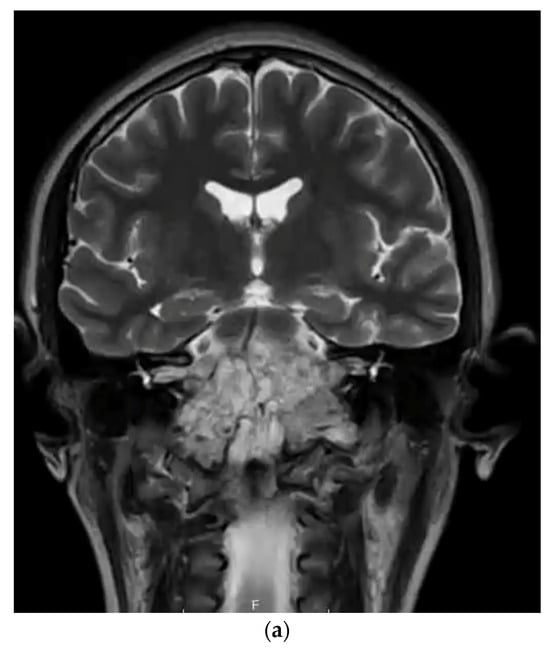

Generally, CH symptoms vary according to its primary anatomic site. Skull base CH often presents with headaches, cranial neuropathies, and vision problems given its central involvement within the clivus, but it is often identified incidentally [7]. Sacral CH often presents with back pain, lower extremity symptoms, and/or bowel/bladder dysfunction from local compression [8]. Radical surgical resection remains the mainstay of modern treatment paradigms for CH [9] with neo-/adjuvant therapies and radiation playing a critical role in disease control [10]. Specifically, skull base CH makes complete excision particularly challenging given its proximity to critical neurovascular structures (Figure 2a,b) [11].

Figure 2.

(a) T2-weighted MRI coronal sequence demonstrating the characteristic hallmarks of a clival chordoma, T2 hyperintensity within the skull base lesion. (b) T1-weighted MRI post-contrast sagittal sequence demonstrating anatomical boundaries of a clival chordoma with ventral brainstem compression. (c) T1-weighted MRI post-contrast sagittal sequence demonstrating gross total resection via endoscopic endonasal approach of clival chordoma.